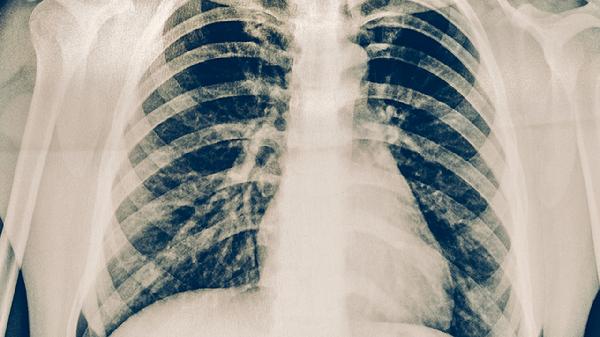

急性血行播散性肺结核的症状主要有高热、寒战、咳嗽、呼吸困难、皮肤瘀点等。急性血行播散性肺结核是结核分枝杆菌通过血液广泛播散至全身多器官的严重感染性疾病,需及时就医治疗。

咳嗽多为干咳或伴有少量粘液痰,当结核杆菌播散至肺部时可引起肺泡和间质炎症反应。咳嗽在夜间或清晨可能加重,严重者可出现痰中带血。治疗需使用抗结核药物如乙胺丁醇片,同时可配合镇咳药物如复方甘草口服溶液缓解症状。

呼吸困难表现为呼吸频率增快、气促,尤其在活动后加重。这与肺部广泛受累导致通气/血流比例失调有关。患者可能出现口唇发绀、三凹征等缺氧表现。治疗需卧床休息、吸氧,并严格遵医嘱使用链霉素注射液等抗结核药物。